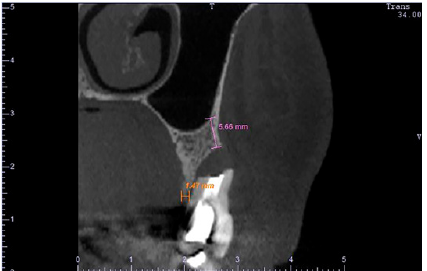

Figure 1: CBCT cross-sectional image of the tooth showing the complete loss of the buccal bone wall. The initial buccal bone height was of 5.66mm (magenta) and the crestal bone thickness was of 1.47mm (orange).